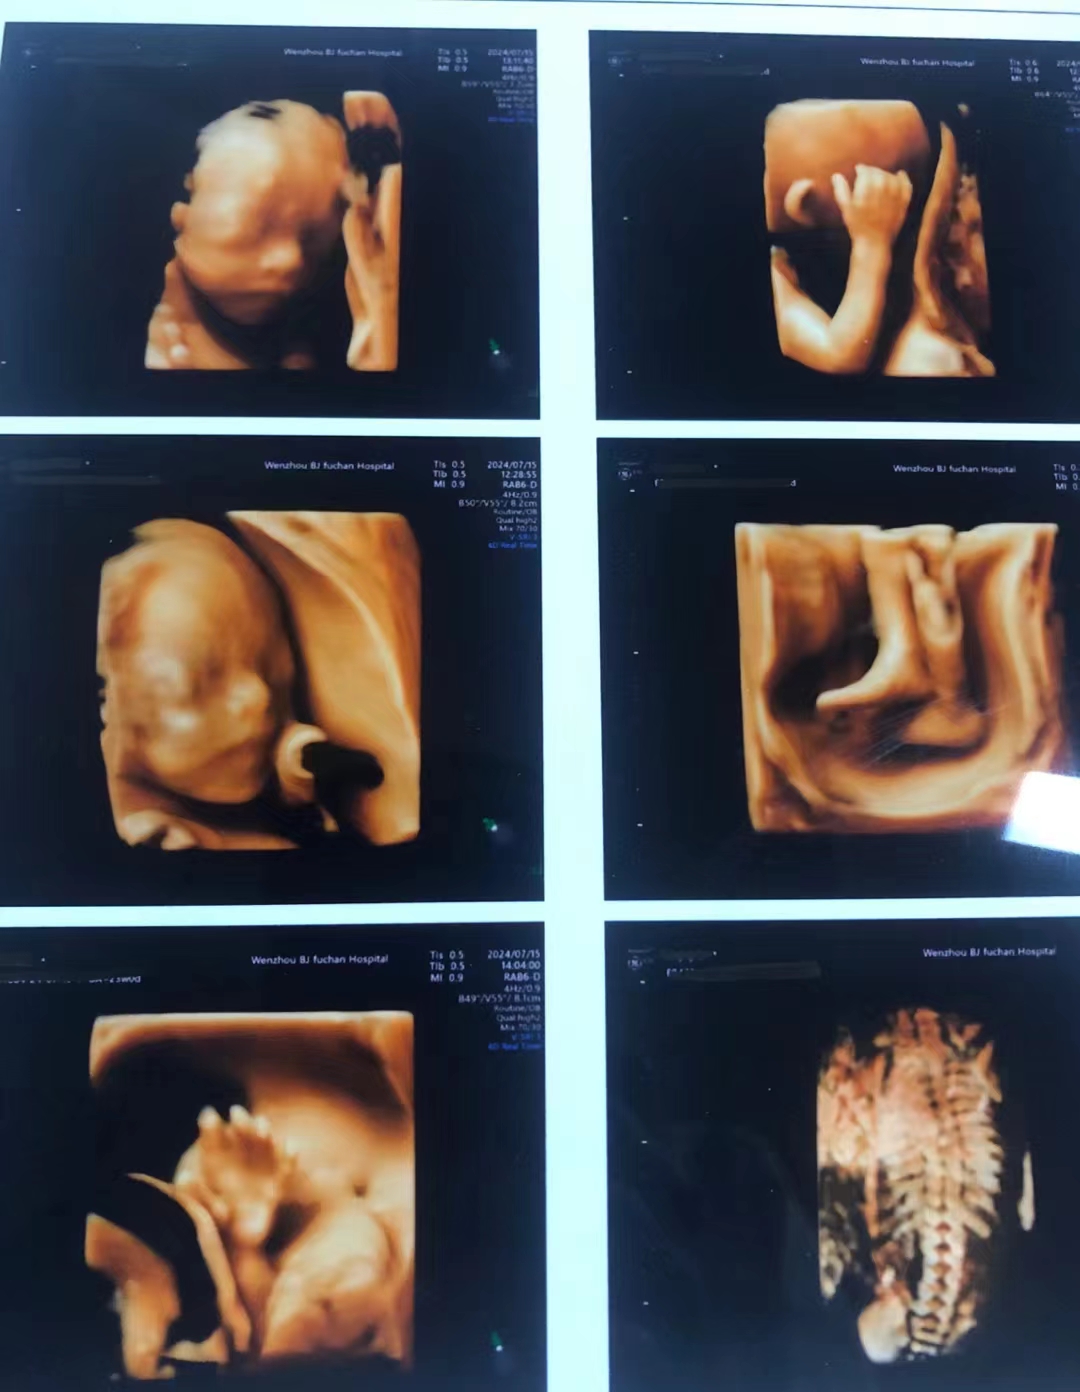

龙港孕妈必看!温州百佳东方四维彩超超全预约攻略!

还在纠结怎么从龙港去温州百佳东方妇产医院做四维彩超?

医院:温州百佳东方妇产医院

地址:温州市鹿城区车站大道79号

1、掐准时间:***黄金期是 22-26周!一定要提前约,别错过时间啦!